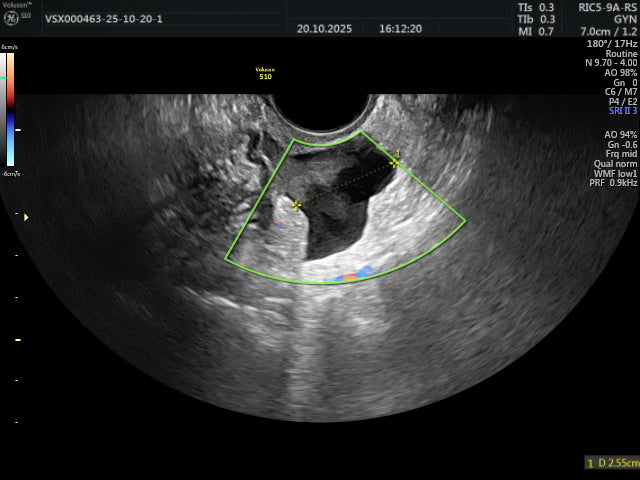

Ultrasoud GE Voluson S10 BT 16 NEW

Ultrasoud GE Voluson S10 BT 16 NEW

GE Voluson S10 BT16 – Advanced 2D/3D/4D Women’s Health & Shared-Service Ultrasound System

The GE Voluson S10 BT16 delivers premium image quality, advanced women’s-health applications, and streamlined workflow in a highly ergonomic design. Built on GE’s Voluson Core Architecture, it is designed for OB/GYN, fetal-maternal, gynecology, and shared-service imaging.

Exceptional Image Quality

Superb 2D clarity and fine detail for more reliable diagnostics.

HDlive™ 3D/4D rendering for exceptional anatomical realism, particularly in fetal imaging.

Advanced imaging tools including OmniView and Advanced Volume Contrast Imaging (VCI) for detailed assessment of irregular anatomy.

Comprehensive Doppler modalities: Color, Power, Tissue Doppler, HD-Flow™, B-Flow, and more.